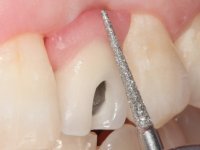

Treatment began with re-preparation of the cast post and core, with the purpose of placing the cervical finishing lines with an intra-sulcular location and simultaneously making a suitable temporary crown. With a very simple orthodontic treatment, the diastema was closed between the upper central incisors, and this position was stabilized with a wire placed on the palatal surface of the central, functioning as containment. Later, a slow orthodontic traction of tooth 2.2 was attempted, in order to reduce, although very slightly, the vertical bone loss in this area. At the end of the traction, tooth 2.2 was extracted and the area was provisionally rehabilitated with a composite resin crown bonded to the adjacent teeth. A dental implant was placed in the area of tooth 2.2 and the temporary crown was again bonded to resin, provisionally rehabilitating the patient during osseointegration. In tooth 1.3 a gingivectomy with an electric scalpel was performed, with the intention of raising the cervical level of 1.3 achieving greater harmony with tooth 2.3. Stabilized soft tissues were impressed using the open tray technique with putty and light addition silicones. Collection of the color of both the dental component and soft tissues was done by the ceramist in the office. In the laboratory, the impressions were transferred to plaster and gave origin to work models that were properly analyzed. It was decided to assemble a metal-ceramic abutment screwed onto the implant. This abutment was cast with a noble alloy and subsequently coated with coronary and gingival ceramics. Due to the inclination of the implant, the screwing inevitably conditioned the exit of the screw hole through the vestibular surface. In order to conceal this situation, the design of the abutment has already been conceived with the intention of accommodating on the vestibular surface the bonding of a feldspathic veneer. This abutment was tested in the mouth and adjustments were made in the gingival ceramic component. Its adaptation to the soft tissues was done in a subtractive way, with a drill, as well as additive, adding resin composed of gingival tonality.

This addition of resin would guide the ceramist in the final placement of the gingival tonality ceramic. The crown that would rehabilitate tooth 1.3 was cemented in this test session with glass ionomer cement, reinforced with composite resin. Once the laboratory work was finished on the veneer for tooth 1.2, the abutment, and the veneer for the implant, this was bonded in the mouth, after placement of the absolute insulation. The work completely satisfied the patient. For eight years, the patient had periodical check-ups, and was pleased with the treatment, but also began to show interest in an aesthetical intervention on the upper central incisors. Once the second phase of our intervention was decided, dental preparation of teeth 1.1 and 2.1 was performed for the placement of two feldspathic veneers. Particular care was taken in the distal inter-proximal preparation adjacent to the abutment of the implant.

The axis of insertion of the veneer in relation to the abutment was very carefully evaluated. The feldspathic veneers were prepared in the laboratory and then bonded to the mouth after placing absolute insulation. One year later, we began our third phase of treatment, after the veneer in tooth 2.1 fractured. A dental preparation was done on the bonded veneer, seeking to extend the distal inter-proximal interface more to the palate. The objective would be to move the veneer to a more palatine contact point. Preparation of tooth 1.2 was limited to creating an insertion axis. After preparation, the total crown and laboratory veneer were bonded to the mouth. First, the crown was bonded using a relative insulation with Teflon, later the veneer was bonded after the absolute insulation placement. In the crown, I used this type of insulation to avoid the use of staples. It would be difficult to apply due to the shape and size of the tooth, and would also be aggressive to the soft tissues. After bonding procedures, the occlusal integration of the work was evaluated.